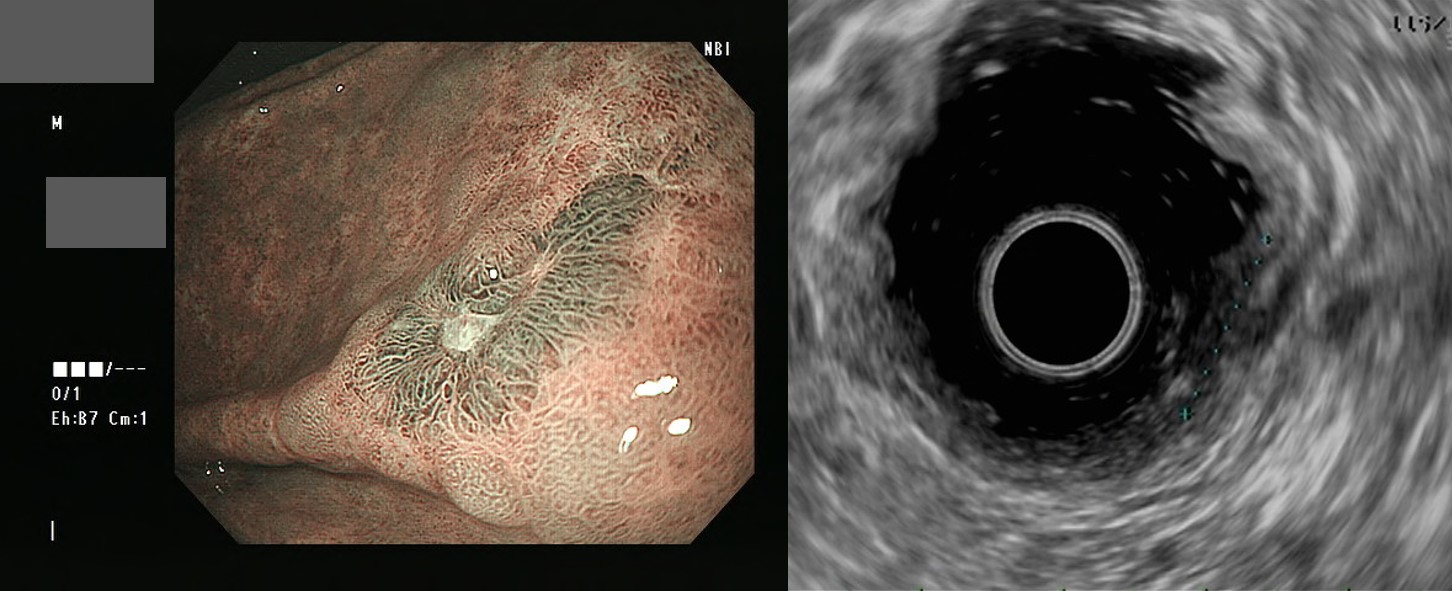

»óºÎÀ§Àå°ü Áúȯ¿¡¼­ ÃÊÀ½ÆÄ ³»½Ã°æÀÇ ¿ªÇÒ (¹Î¾ç¿ø)